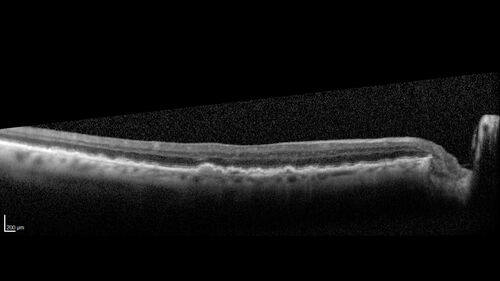

Conversion to Wet AMD after Izervay

83 year old man whose left eye had minimal GA and converted from dry to wet AMD after a single Izervay treatment